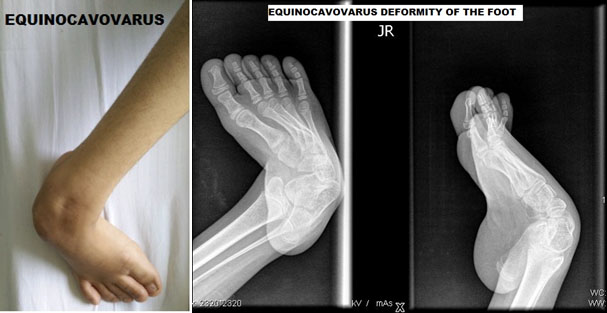

ORTHOPEDIC SURGERY OF THE FOOT

Cavovarus

Cavovarus is of slightly lesser incidence, and it is there opposite of flat foot. In this condition, the foot is turned inside; the position is described as supination. The child walks on the outer border of the feet and develops callosities on the outer edge. If the child has a persistent pain because of this, then it would require a tendon transfer to balance the muscle forces. The tendon transfer is called “Split transfer of the tibialis posterior.”